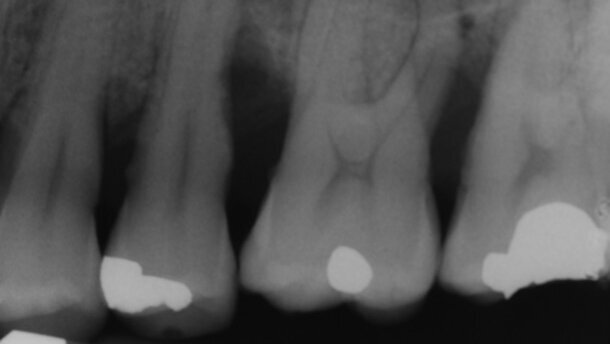

I valori del sondaggio erano generalmente nella norma, fatta eccezione per la zona mascellare, di sinistra (Figg. 2, 3). È stato eseguito uno status radiografico completo. La radiografia periapicale evidenzia un difetto osseo verticale significativo, localizzato distalmente al secondo premolare (Fig. 1). Il sondaggio iniziale era di 11 mm, associato a sanguinamento (Fig. 2). La sonda parodontale rileva abbondanti depositi calcificati, in sede sotto gengivale (Fig. 3). Il paziente riferiva di essere in cura presso un altro dentista e di sottoporsi a sedute di igiene professionale ogni 6 mesi. Il paziente viene sottoposto a terapia causale, secondo un protocollo che prevede tre sedute ravvicinate, con l’uso aggiuntivo del laser a diodo 808 nm (1 Watt in modalità pulsata – pw – equivalente a 0.5 W in modalità continua – cw – per 30 sec. in ciascun sito in duplicato, 360 secondi in totale, fluenza: 62 J/cm2, frequenza: 10 Hz) entro una settimana, e una quarta seduta nell’arco di 30 giorni circa6.

Si programma un ulteriore appuntamento, ravvicinato, per controllare l’effettiva rimozione della noxa patogena e motivare il paziente a una congrua igiene domiciliare, in occasione del quale si utilizza di nuovo il laser a diodo 980 nm, (Wiser, Doctor Smile, Lambda S.p.A.,Vi, Italy), con gli stessi parametri, utilizzati dell’appuntamento precedente: potenza 2.5W - media 0.7W - 10 kHz; modalità pulsata (pw) Ton =30μs Toff=70μs per 30 sec., in ciascun sito in duplicato, fluenza: 120 J/cm2, sempre in associazione alla strumentazione parodontale non chirurgica, secondo necessità (Fig. 7). Si esegue un sondaggio delicato del sito, che rileva un miglioramento dell’infiammazione. Si ipotizza la presenza di una “pocket closure”9: l’inserto del laser, infatti, non riesce a penetrare oltre i 2 mm nel solco parodontale (Fig. 8). Si decide per l’utilizzo del laser a diodo, in occasione di una seconda seduta a pochi giorni di distanza dalla prima, allo scopo di stabilizzare i risultati ottenuti6 e per favorire la guarigione, con la formazione di un epitelio di giunzione lungo10. Alla rivalutazione parodontale, dopo sei mesi dal trattamento della recidiva, si rileva una profondità di sondaggio nella norma, in assenza di sanguinamento (Figg. 9, 10). La radiografia (Fig. 11) documenta una migliore qualità del supporto osseo e la presenza di una lamina dura più rappresentata. In particolare, in sede interprossimale tra il primo e il secondo molare mascellare di sinistra, non è più presente la “freccia radio trasparente”, indicativa di una compromissione della biforcazione distale11.